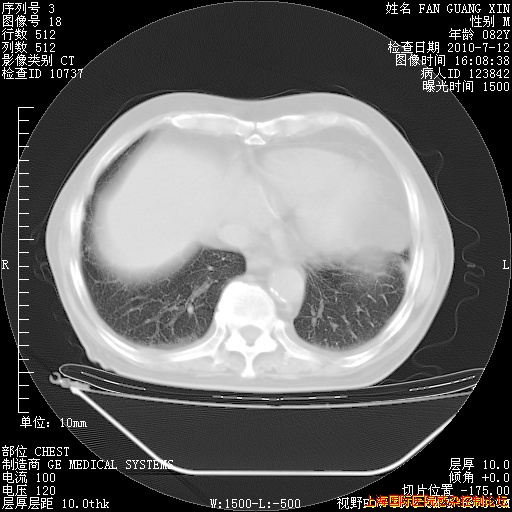

6月12日纵膈窗